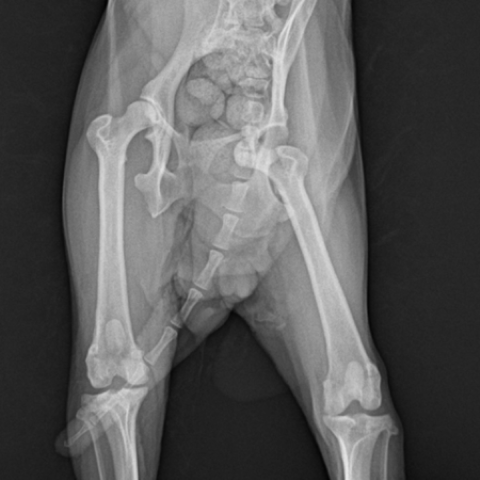

½½°³°ñ Å»±¸ ¼ö¼ú Àü